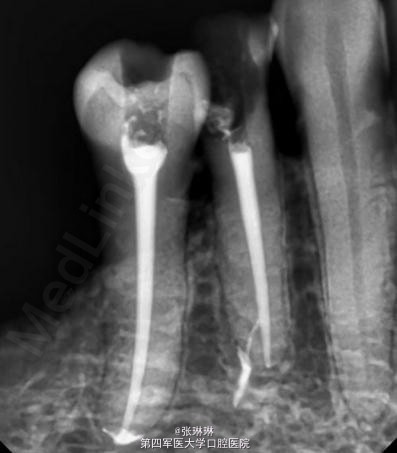

根据龋坏程度、患者的症状、修复需要,且对收费及牙髓处理均征得同意后第一次行右下4、5,左下4、5、6;第二次行左下2,右下2 ,右上7一次性根管治疗术, 术后见右下4,左下4均有侧支充填,且位置对称,左下6近中根中部有侧支;左下5、左下6远中根管均多个开口。 热牙胶垂直加压后有封闭剂和牙胶超填,但无术后反应。